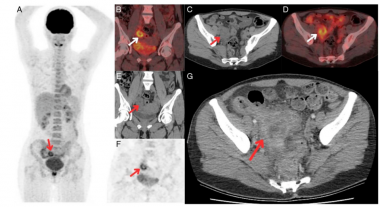

医学领域

更多>

在线四维影像引导立体定向及自适应放疗技术推广应用项目正式启动